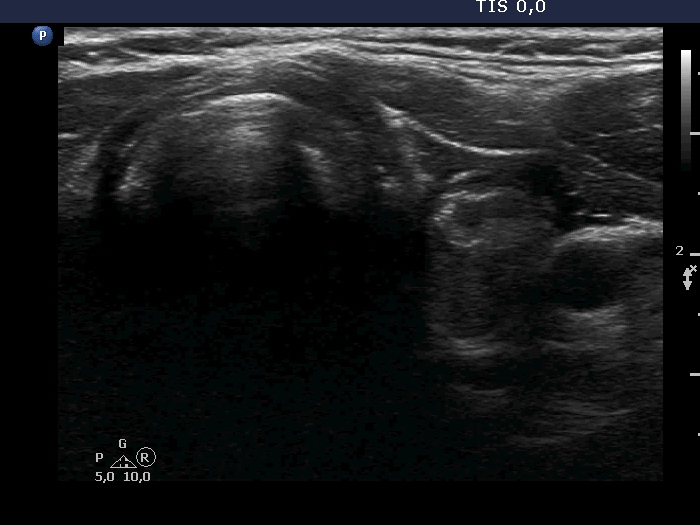

A conglomerate of lymph nodes was found 2 cm above the left lobe. The nodes did not have hilum but contained microcalcifications and presented irregular vascular pattern. (This was not noticed on the previous ultrasound examination.)